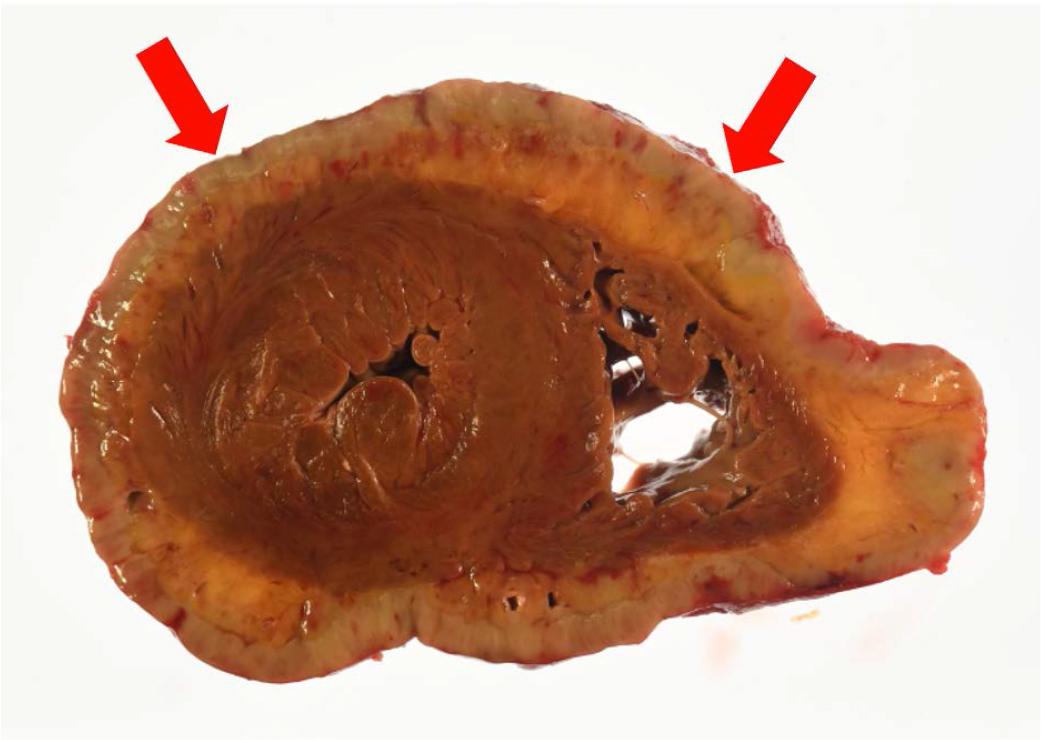

Autopsy results. A diffuse, greenish-white neoplastic lesion approximately 5 mm wide and circumferential to the epicardium was observed (Figure 3), with a histological infiltrate of atypical cells with a high nucleocytoplasmic ratio. The epicardial dysplastic cells were mostly MPO(+), CD34(+), c-kit(−), p53(−), CD68(Kp-1)(−), CD68(PG-M1) (−), CD4(+), CD15(+), CD99(−), and TdT(−), suggesting a myelosarcoma.

Cross-section of the heart at autopsy. Diffuse greenish-white neoplastic lesions extending circumferentially and diffusely around the pericardial epicardium (red arrow).